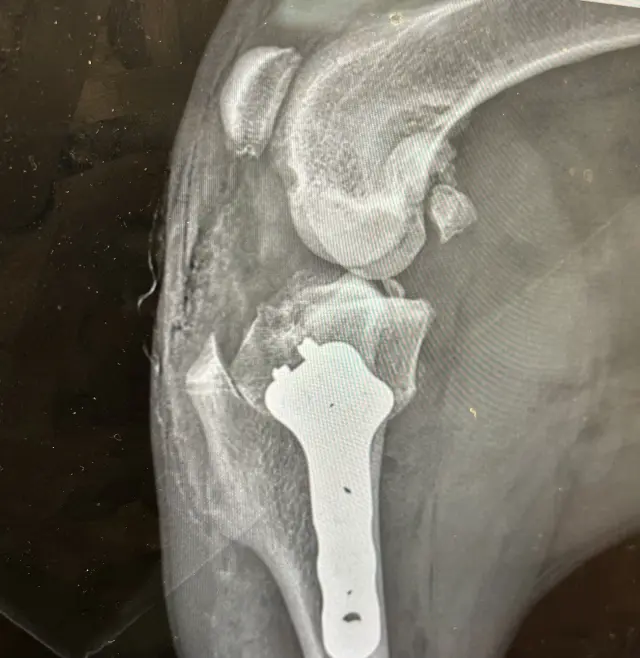

Už minulý rok mala Lola problémy so vstávaním zo zeme a sadaním si, a preto sme jej dali spraviť röntgen. Veterinár nám vtedy povedal, že má všetko v poriadku – kosti aj kĺby – a že dysplázia u nej nehrozí. Dnes už vieme, že snímky boli urobené nesprávne, v zlej polohe, a kvôli tomu sme stratili drahocenný čas.

Lola dnes trpí dyspláziou bedrových kĺbov, artrózou a vážnym poškodením väzov v oboch kolenách. Potrebuje dve operácie: najskôr ľavé koleno, neskôr pravé. Je to ako domino efekt – čím dlhšie budeme čakať, tým viac sa jej stav zhorší a vznikne ďalšie poškodenie.

Veterinárna diagnostika odhalila dyspláziu bedrových kĺbov, chronické pretrhnutie väzov v oboch kolenách a pokročilú artrózu. Každý krok ju bolí, a hoci sa snaží byť veselá, vidno, že trpí.